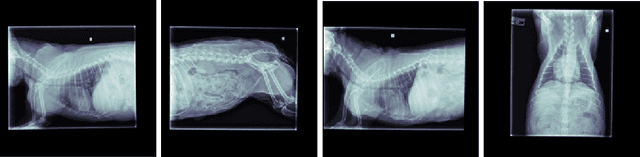

Abstract:Self-supervised learning has emerged as a powerful paradigm for training deep neural networks, particularly in medical imaging where labeled data is scarce. While current approaches typically rely on synthetic augmentations of single images, we propose VET-DINO, a framework that leverages a unique characteristic of medical imaging: the availability of multiple standardized views from the same study. Using a series of clinical veterinary radiographs from the same patient study, we enable models to learn view-invariant anatomical structures and develop an implied 3D understanding from 2D projections. We demonstrate our approach on a dataset of 5 million veterinary radiographs from 668,000 canine studies. Through extensive experimentation, including view synthesis and downstream task performance, we show that learning from real multi-view pairs leads to superior anatomical understanding compared to purely synthetic augmentations. VET-DINO achieves state-of-the-art performance on various veterinary imaging tasks. Our work establishes a new paradigm for self-supervised learning in medical imaging that leverages domain-specific properties rather than merely adapting natural image techniques.

Abstract:Chest X-ray images are commonly used in medical diagnosis, and AI models have been developed to assist with the interpretation of these images. However, many of these models rely on information from a single view of the X-ray, while multiple views may be available. In this work, we propose a novel approach for combining information from multiple views to improve the performance of X-ray image classification. Our approach is based on the use of a convolutional neural network to extract feature maps from each view, followed by an attention mechanism implemented using a Vision Transformer. The resulting model is able to perform multi-label classification on 41 labels and outperforms both single-view models and traditional multi-view classification architectures. We demonstrate the effectiveness of our approach through experiments on a dataset of 363,000 X-ray images.

Abstract:This work describes the development and real-world deployment of a deep learning-based AI system for evaluating canine and feline radiographs across a broad range of findings and abnormalities. We describe a new semi-supervised learning approach that combines NLP-derived labels with self-supervised training leveraging more than 2.5 million x-ray images. Finally we describe the clinical deployment of the model including system architecture, real-time performance evaluation and data drift detection.